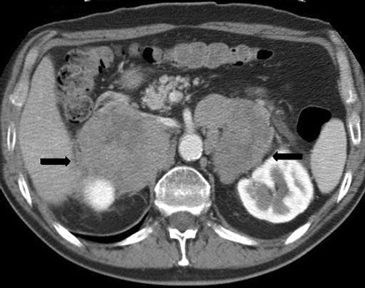

En la TC no contrastada las glándulas suprarrenales normales son homogéneas y simétricas, con una densidad muy similar a la del parénquima renal adyacente (Figura 1 a). Con un medio de contraste ev la glándula suprarrenal se opacifica en forma homogénea, similar al hígado o al bazo (Figura 1 b). Si la cantidad de tejido adiposo retroperitoneal es abundante las glándulas suprarrenales pueden aparecer enteramente rodeadas por grasa y su delimitación es más fácil (Figura 2 a); lo inverso ocurre en pacientes muy delgados con escasa grasa retroperitoneal (Figura 2 b). En RM, en secuencias ponderadas en T1 y T2 convencionales tienen una intensidad de señal homogénea, hipointensa respecto de la grasa adyacente e iso o hipointensa con respecto del parénquima hepático (Figura 3 a y b). En los cortes coronales se aprecia mejor la forma y la posición de las glándulas suprarrenales (Figura 3 c).

Figura 1. Glándula suprarrenal normal en tomografía computada. Cortes axiales de tomografía computada, donde se identifica la morfología normal de la glándula suprarrenal derecha (flecha) en fase no contrastada (a), y tras el uso de medio de contraste endovenoso (b).